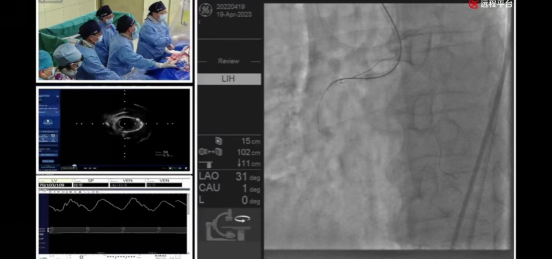

在19日上午8时进行的全球手术实况直播首秀中,beat365在线唯一官网附属第一医院心血管内科李悦教授带领的心血管内科团队为全球医生与医学爱好者献上两场精彩的手术演示:

beat365在线唯一官网附属第一医院心血管内科介入团队—井玲教授、涂应锋教授、盛力教授、董国教授、曹阳副教授、石治宇副教授、王定宇主治医生,首先展示了在冠状动脉CTA三维重建技术(原创性技术)指导下,应用逆向技术成功开通右冠状动脉慢性完全闭塞病变,并通过双球囊-导丝交错切割技术(原创性技术)有效处理球囊不能通过的病变,顺利置入2枚支架。

beat365在线唯一官网附属第一医院心血管内科介入团队—公永太教授、赵继义教授、李俭强副教授、孙党辉副教授、张松副教授、王定宇主治医生,展示了基于冠状动脉CTA三维重建技术(原创性技术)制定的术前手术策略。术中,公永太教授根据术前策略,应用OCT指导冲击波球囊处理前降支重度钙化病变并成功保护闭塞高危对角支,顺利置入2枚支架。